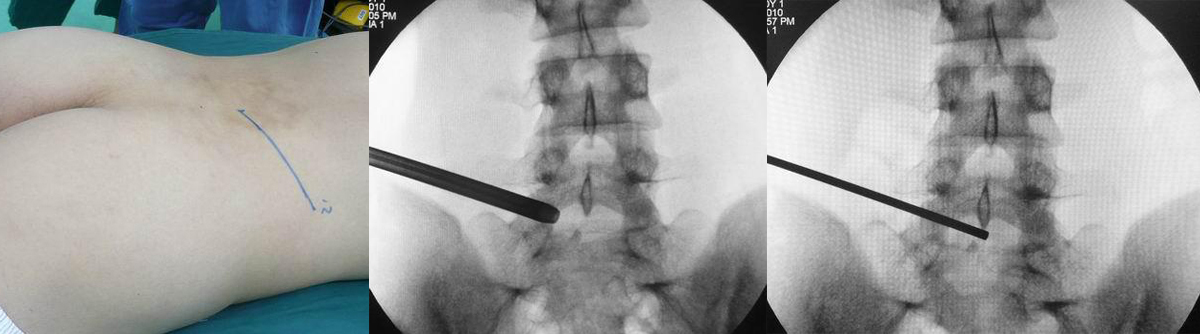

经典病例一

高* 女,腰痛伴左臀部疼痛麻木,左足麻木半月。

查体:腰5骶1棘间及左棘旁压痛、叩痛明显,疼痛向左臀部放射,左臀部外侧及左足底皮肤感觉减退,左跟腱反射减弱,左侧直腿抬高试验阳性(40°),加强试验阳性。

腰椎MRI示:L5S1椎间盘突出,左侧神经根受压。

(图)体表定位

(图)穿刺针定位

(图)置入扩张管